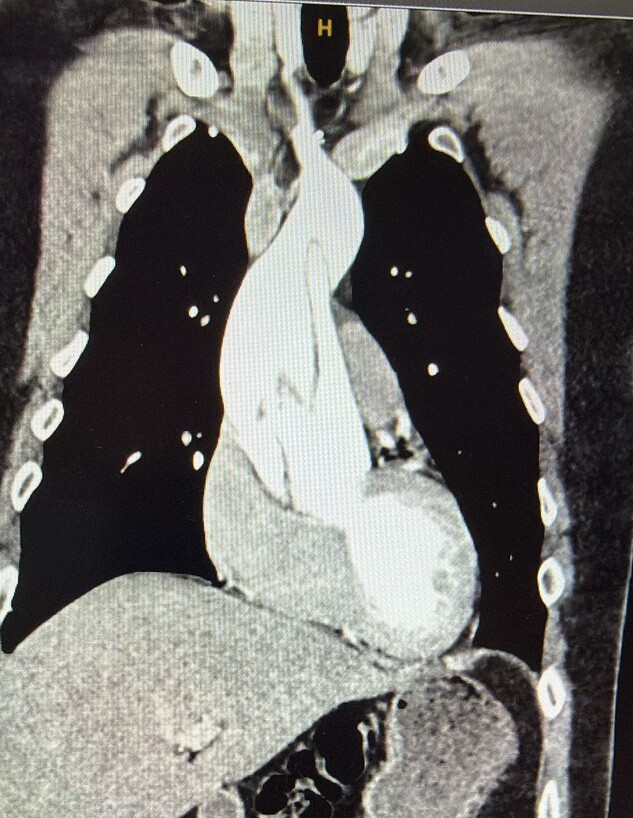

לאחר ייצוב מצבה ומחשש לשלום העובר, הוחלט על ניתוח קיסרי דחוף. התינוק, שנולד בשבוע ה-29, הועבר לפגייה ואושפז במשך שלושה חודשים. לאחר הטיפול השתחררה האם במצב טוב וכך גם בנה. בבדיקות שנעשו לאחר מכן אובחנה אצל האם תסמונת מרפן, תסמונת תורשתית הפוגעת בין היתר בכלי הדם ובלב. הבן אובחן גם הוא עם אותה תסמונת גנטית. במשך השנים הבן והאם היו במעקב כדי למנוע החמרה במצבם.

סגן א', משרת כיום כקצין ביחידה מסווגת בצה"ל וחש לאחרונה החמרה במצבו. הרופאים חששו לנזק בדופן הלב והוא הגיע לבית החולים שערי צדק לניתוח דחוף. גם הפעם, את הניתוח של א' ביצע ד"ר דני פינק, שניתח את האם בהיותה בהיריון לפני 21 שנים, וכיום מנהל את המחלקה לכירורגיית לב במרכז הרפואי שערי צדק. הניתוח עבר בהצלחה, סגן א' השתחרר במצב טוב ונמצא בשיקום לקראת חזרתו לשירות בצה"ל.

סגן א' מספר: "ידעתי במשך השנים על סיפור הלידה המיוחד שלי, ועל התסמונת שיש לי. לא נתתי לתסמונת לעצור אותי בשום שלב בחיים. הייתי כל השנים במעקב אבל לא היו שינויים במצבי. 21 שנים אחרי, מספר ימים לפני שהייתי צריך לעבור בדיקת מעקב שגרתית, חשתי בכאבים חריגים באופן קיצוני והגעתי לבית החולים שערי צדק. הרופאים זיהו קרע באבי העורקים, ושוב הוזעק מביתו ד״ר פינק לניתוח חירום, שהציל את חיי בדיוק כמו שקרה 21 שנה קודם לכן שהציל את חייה של אימי"./